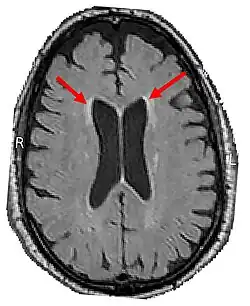

Brain CT of brain showing white matter lesions (indicated by the red arrows)

4. Brain CT/MRI findings:

1. Bilateral Cerebral white matter lesions[11]

2. Thinning of the Corpus Callosum[11]